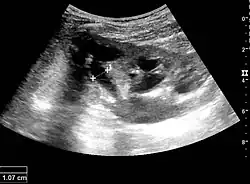

Cortical thickness should be estimated from the base of the pyramid and is generally 7–10 mm. If the pyramids are difficult to differentiate, the parenchymal thickness can be measured instead and should be 15–20 mm (Figure 3). The echogenicity of the cortex decreases with age and is less echogenic than or equal to the liver and spleen at the same depth in individuals older than six months. In neonates and children up to six months of age, the cortex is more echogenic than the liver and spleen when compared at the same depth.[1]